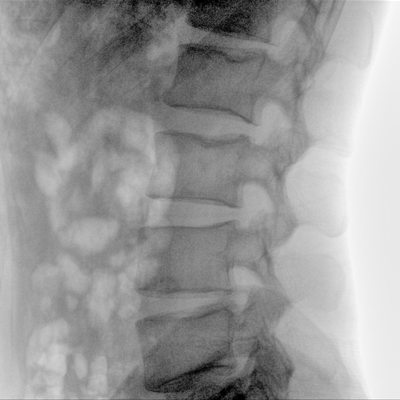

Clinical picture

临床图片

骨科: 经皮锥体成形术、经皮椎间盘臭氧治疗术、胸脊椎固定、骨活检、腰椎内固定术等。